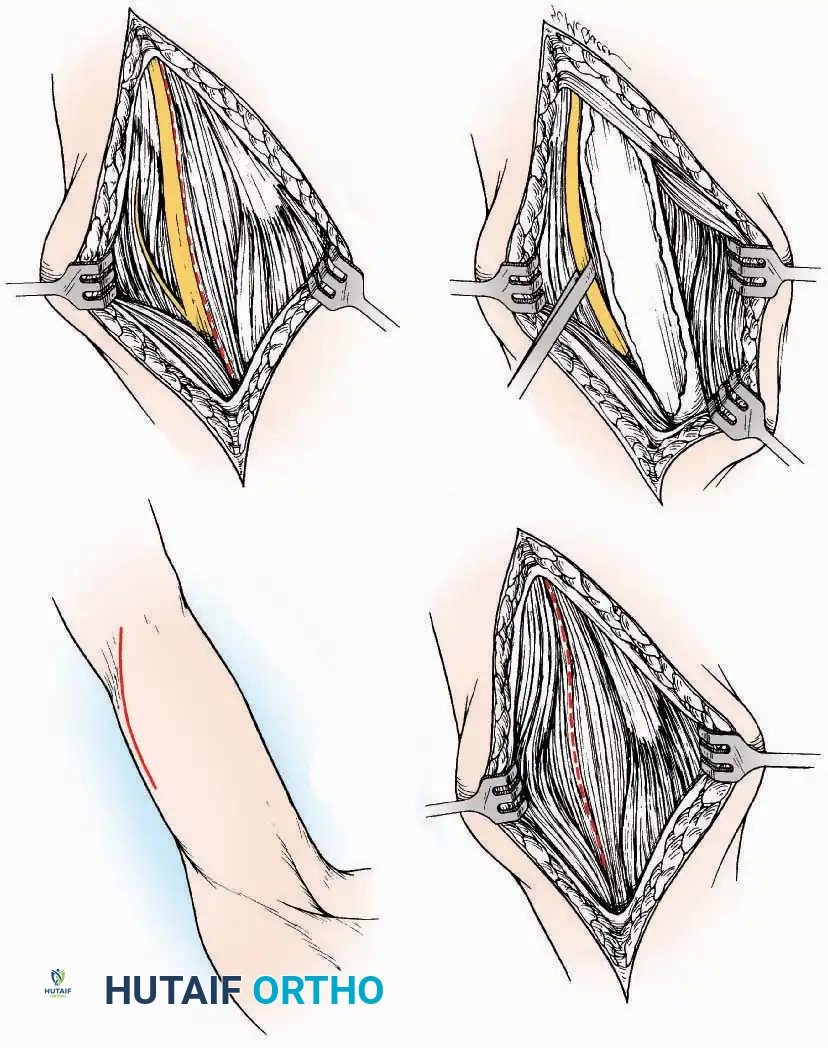

Anterior Approach

Indications: Total ankle arthroplasty (TAA), anterior ankle arthrodesis, and excision of anterior tibial/talar osteophytes (anterior impingement).

💡 Clinical Pearl

Gaining access to the medial gutter (the articulation between the medial malleolus and the medial articular facet of the talus) can be challenging through a pure anterior approach. Meticulous medial subperiosteal dissection of the joint capsule is required to avoid excessive traction on the anterior neurovascular bundle.

Surgical Technique:

* Incision: Make a 10 to 15 cm longitudinal incision over the anterior aspect of the ankle, centered exactly midway between the medial and lateral malleoli.

* Superficial Dissection: Incise the superficial fascia. Identify and protect the superficial peroneal nerve branches laterally and the saphenous nerve medially.

* Internervous Plane: The deep dissection exploits the plane between the Extensor Hallucis Longus (EHL) tendon (innervated by the deep peroneal nerve) and the Extensor Digitorum Longus (EDL) tendons (also innervated by the deep peroneal nerve).

* Neurovascular Bundle: Incise the extensor retinaculum. Carefully identify the anterior tibial artery and the deep peroneal nerve, which typically lie between the EHL and EDL, or directly deep to the EHL. Retract the neurovascular bundle laterally with the EDL, or medially with the EHL, depending on the specific anatomical variant encountered (lateral retraction is most common).

* Capsulotomy: Incise the anterior joint capsule longitudinally. Elevate the capsule subperiosteally from the anterior tibia and the talar neck to expose the entire tibiotalar articulation.